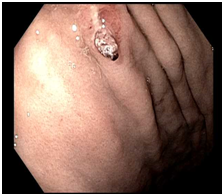

A 71year old woman with a past medical history of hypertension, gastroesophageal reflux disease and chronic epigastric pain was presented to the emergency room with complaint of melena and dizziness. She had undergone upper GI endoscopy and colonoscopy as an outpatient the day prior to presentation. Her upper GI endoscopy revealed a normal esophagus, stomach and duodenum. Biopsies of the gastric body and antrum were taken for evaluation of Helicobacter Pylori. She reported doing well after the procedures and was subsequently discharged from the endoscopy center. She was able to tolerate dinner that evening, but immediately had a large watery melenic stool. Furthermore, the morning prior to presentation, she experienced dizziness and lightheadedness, resulting in her admittance to the emergency room. The patient’s hemoglobin was found to be 6.7g/dL, which was down from her baseline of 12.7g/dL in January of 2016. Upper GI endoscopy revealed several linear erosions consistent with prior biopsy sites in the gastric body and antrum. One of these linear lesions had a prominent protruding non-bleeding visible vessel, which was subsequently washed thoroughly and treated with a hemoclip. The patient was then placed on Pantoprazole and monitored for 48hours in the hospital, with steady hemoglobin. In addition, she did not experience any melenic stools while in the hospital, and later was discharged home in stable condition (Figure 1) (Figure 2).

Figure 1